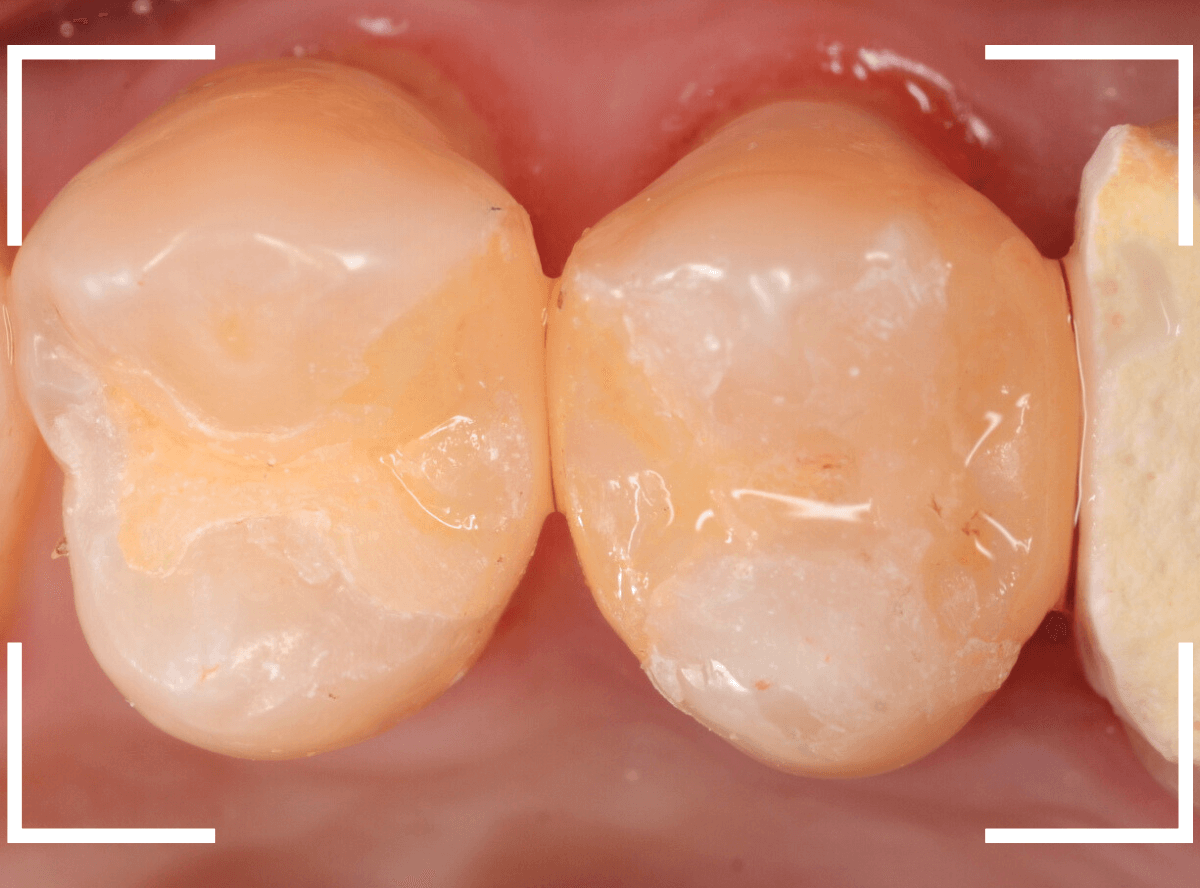

Case.28 虫歯治療後、半年以上来院されなかった患者さん

虫歯を治療して、セメントで歯を削った部分を封鎖した後、再修復を検討中で、半年以上来院されなかった患者さんです。

虫歯を治療して、セメントで封鎖した状態というのは、家でいえば、しっかりした屋根がない状態です。

今回は、セメントの一部がはがれる程度で済んでいましたが、虫歯が再発し、再治療、最終修復物の変更の可能性も出てきます。

治療再開後、セラミックの最終修復を希望されましたので、歯をトリミングし、型取りします。

治療後の状態です。